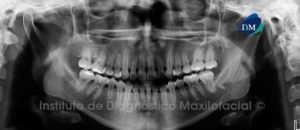

Paciente masculino, 12 años de edad es referido al Instituto de Diagnóstico Maxilofacial (IDM) para evaluación general.A la evaluación de la radiografía panorámica se aprecia

Paciente masculino, 11 años de edad es referido al Instituto de Diagnostico Maxilofacial (IDM) para evaluación general.A la evaluación de la radiografía panorámica (ortopantomografía) se

Paciente femenino, 26 años de edad es referido al Instituto de Diagnóstico Maxilofacial (IDM) para evaluación radiográfica de terceras molares.A la evaluación de la radiografía

Paciente femenino, 23 años de edad es referido al Instituto de Diagnóstico Maxilofacial (IDM) para realizar su estudio previo al tratamiento de ortodoncia.A la evaluación